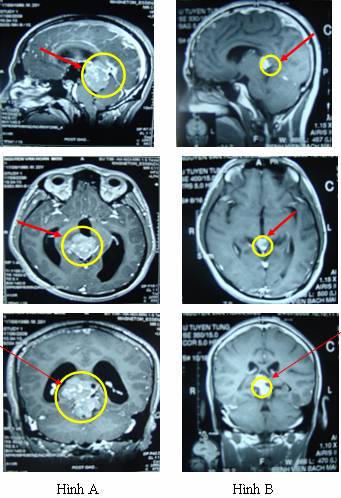

Hình A: Trước xạ trị, khối u vùng tuyến tùng kích thước 5,2x4,8cm, chèn ép não thất 3 gây giãn não thất.

Hình B: Sau điều trị xạ trị 2 tháng, đường kính khối u thu nhỏ còn khoảng 1 cm, hết giãn não thất